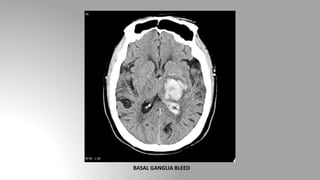

• There are two types of hemorrhagic strokes: those caused by an

intracerebral hemorrhage (ICH) and those caused by a subarachnoid

hemorrhage (SAH)

• Common locations: Basal ganglia and thalamus, pons and cerebellar

hemisphere

• Acute blood is markedly hyperdense compared to brain parenchyma,

and as such usually poses little difficulty in diagnosis.

CT in cerebrovascular accident (CVA)

Hemorrhagic stroke

BASAL GANGLIA BLEED

• There aretwo types of hemorrhagic strokes: those caused by an intracerebral hemorrhage (ICH) and those caused by a subarachnoid hemorrhage (SAH) • Common locations: Basal ganglia and thalamus, pons and cerebellar hemisphere • Acute blood is markedly hyperdense compared to brain parenchyma, and as such usually poses little difficulty in diagnosis. CT in cerebrovascular accident (CVA) Hemorrhagic stroke